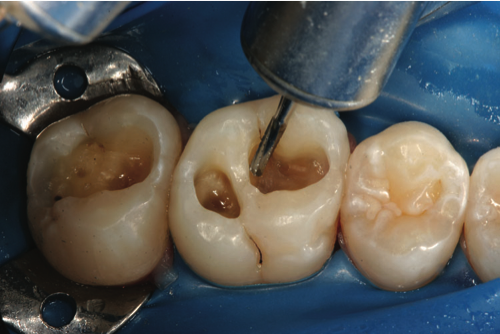

The sectional matrix of dead-soft stainless steel is placed (Figure 9).

Fig 9. Sectional matrix placement.

Figure 9